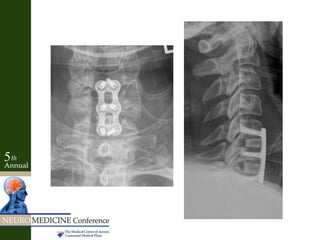

Anterior Cervical Discectomy

and Fusion

C5

C6

Key Factors • Neckpain and “radiculopathy” into arms • Interscapular pain – Cloward 1959- Disc herniations of lower cervical levels induced spasms of para-scapular muscles • Motor/sensory exam not localizing • Myelopathic with hyperactive reflexes • Negative Spurling’s • Positive discogram – Reproduced pain at levels and no pain at adjacent levels • Concordant MRI

• 38.

• 39.